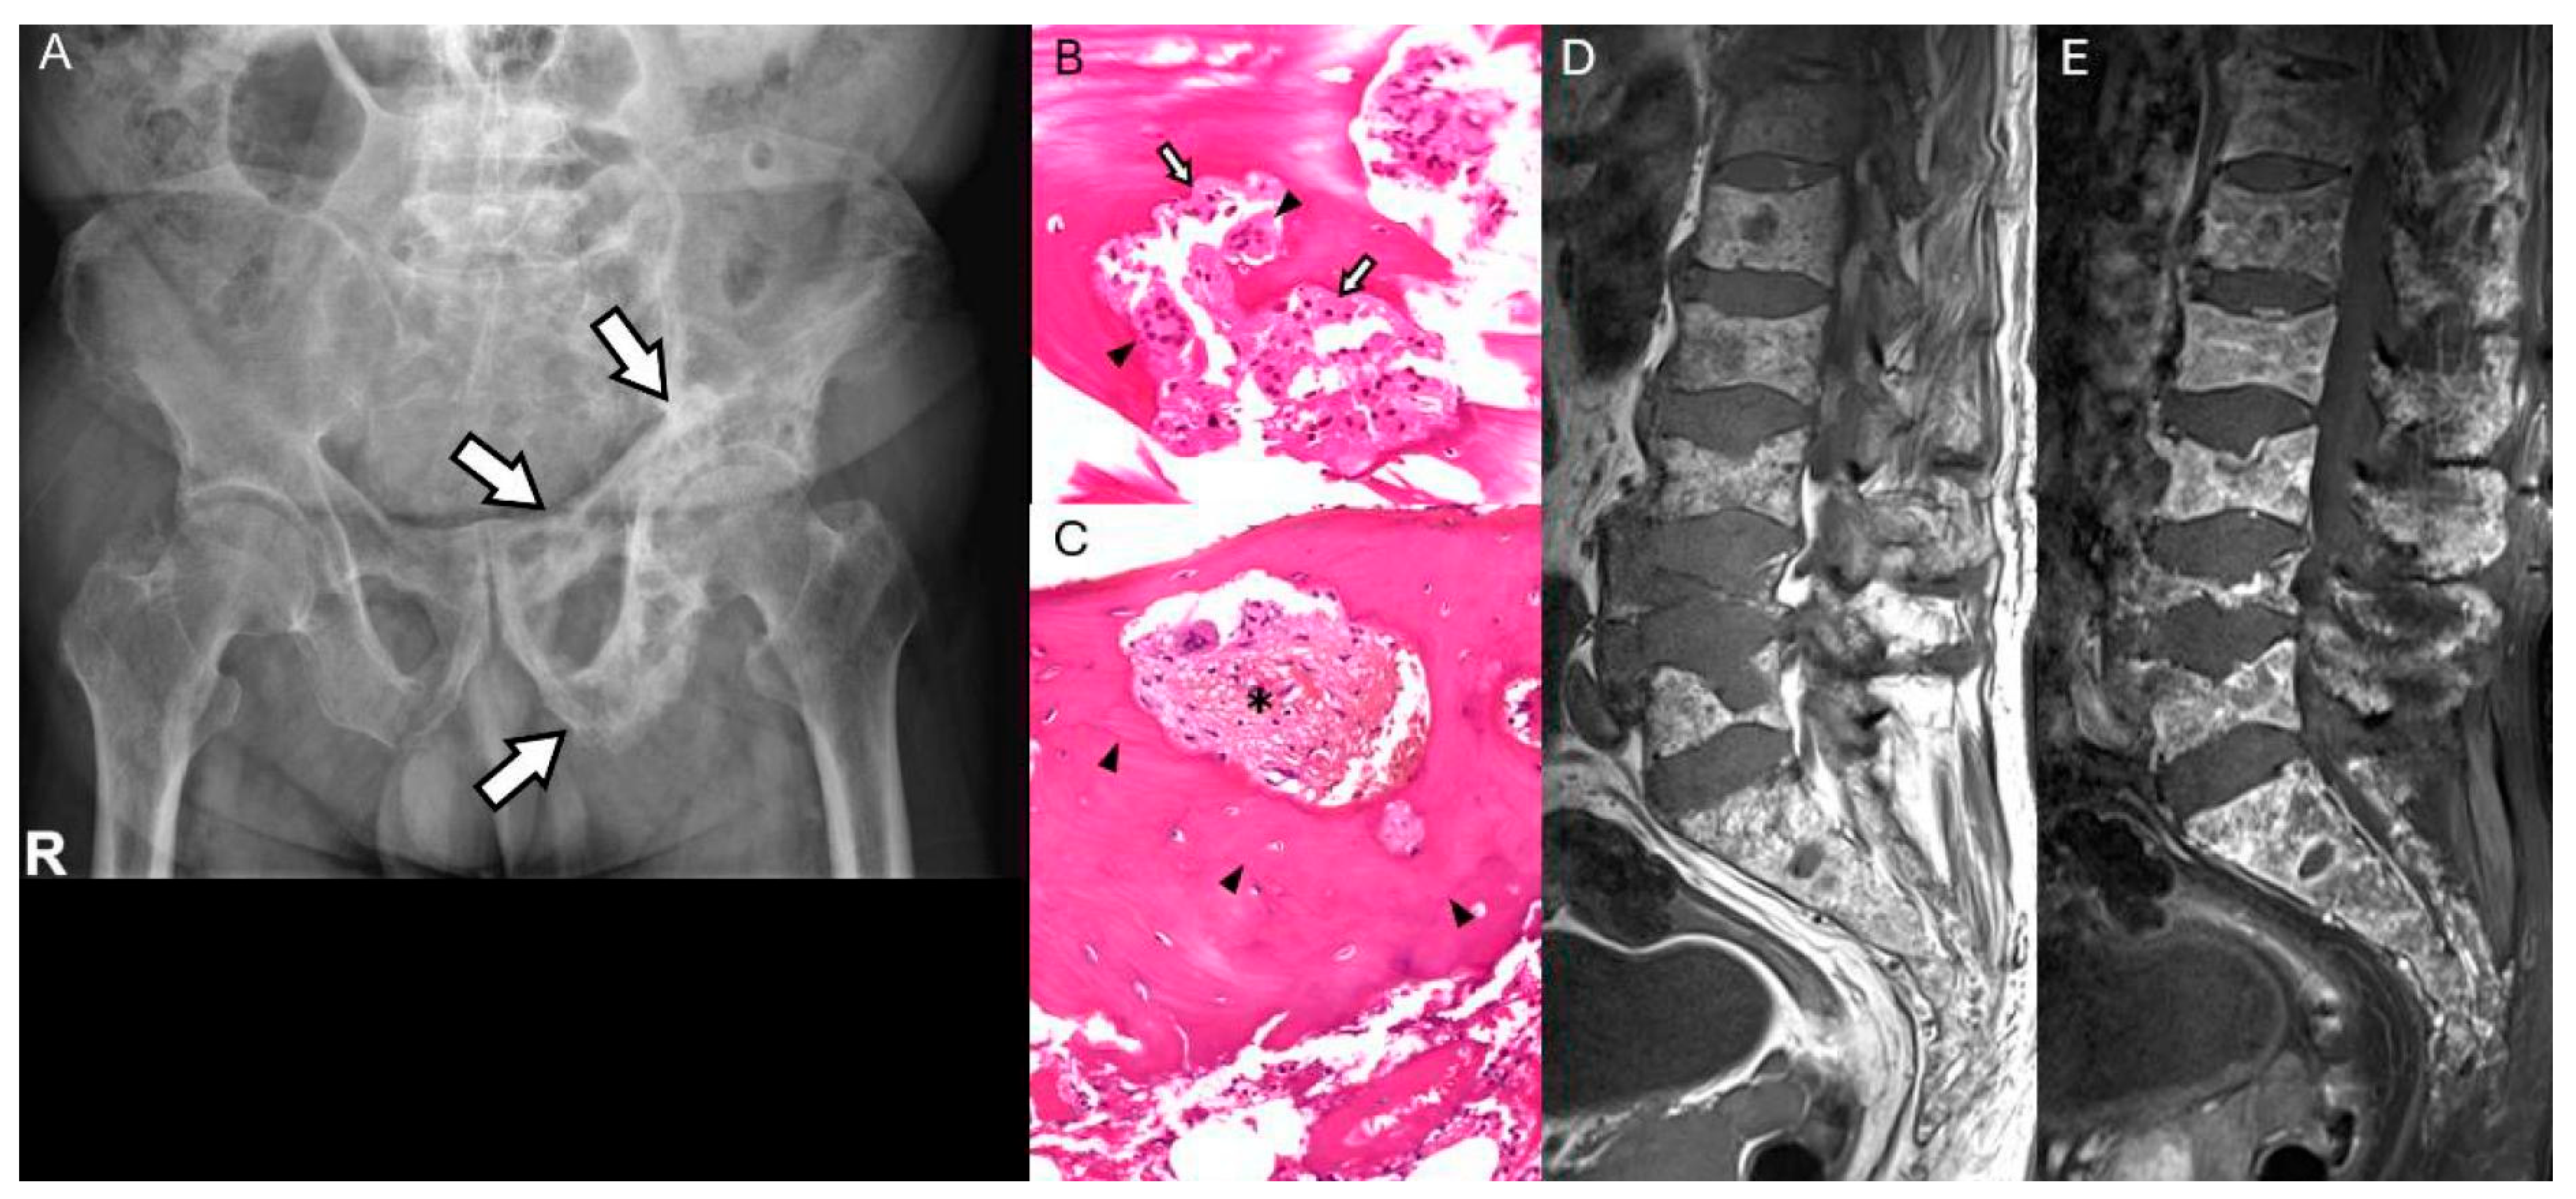

3.4. Paget’s Disease of Bone